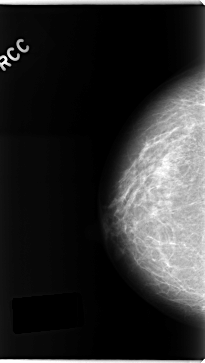

ics_version 1.0 filename C-0241-1 DATE_OF_STUDY 22 2 1995 PATIENT_AGE 63 FILM FILM_TYPE REGULAR DENSITY 2 DATE_DIGITIZED 28 4 1998 DIGITIZER LUMISYS LASER SEQUENCE LEFT_CC LINES 4752 PIXELS_PER_LINE 2624 BITS_PER_PIXEL 12 RESOLUTION 50 OVERLAY LEFT_MLO LINES 4744 PIXELS_PER_LINE 2512 BITS_PER_PIXEL 12 RESOLUTION 50 OVERLAY RIGHT_CC LINES 4712 PIXELS_PER_LINE 2656 BITS_PER_PIXEL 12 RESOLUTION 50 NON_OVERLAY RIGHT_MLO LINES 4728 PIXELS_PER_LINE 2656 BITS_PER_PIXEL 12 RESOLUTION 50 NON_OVERLAY |